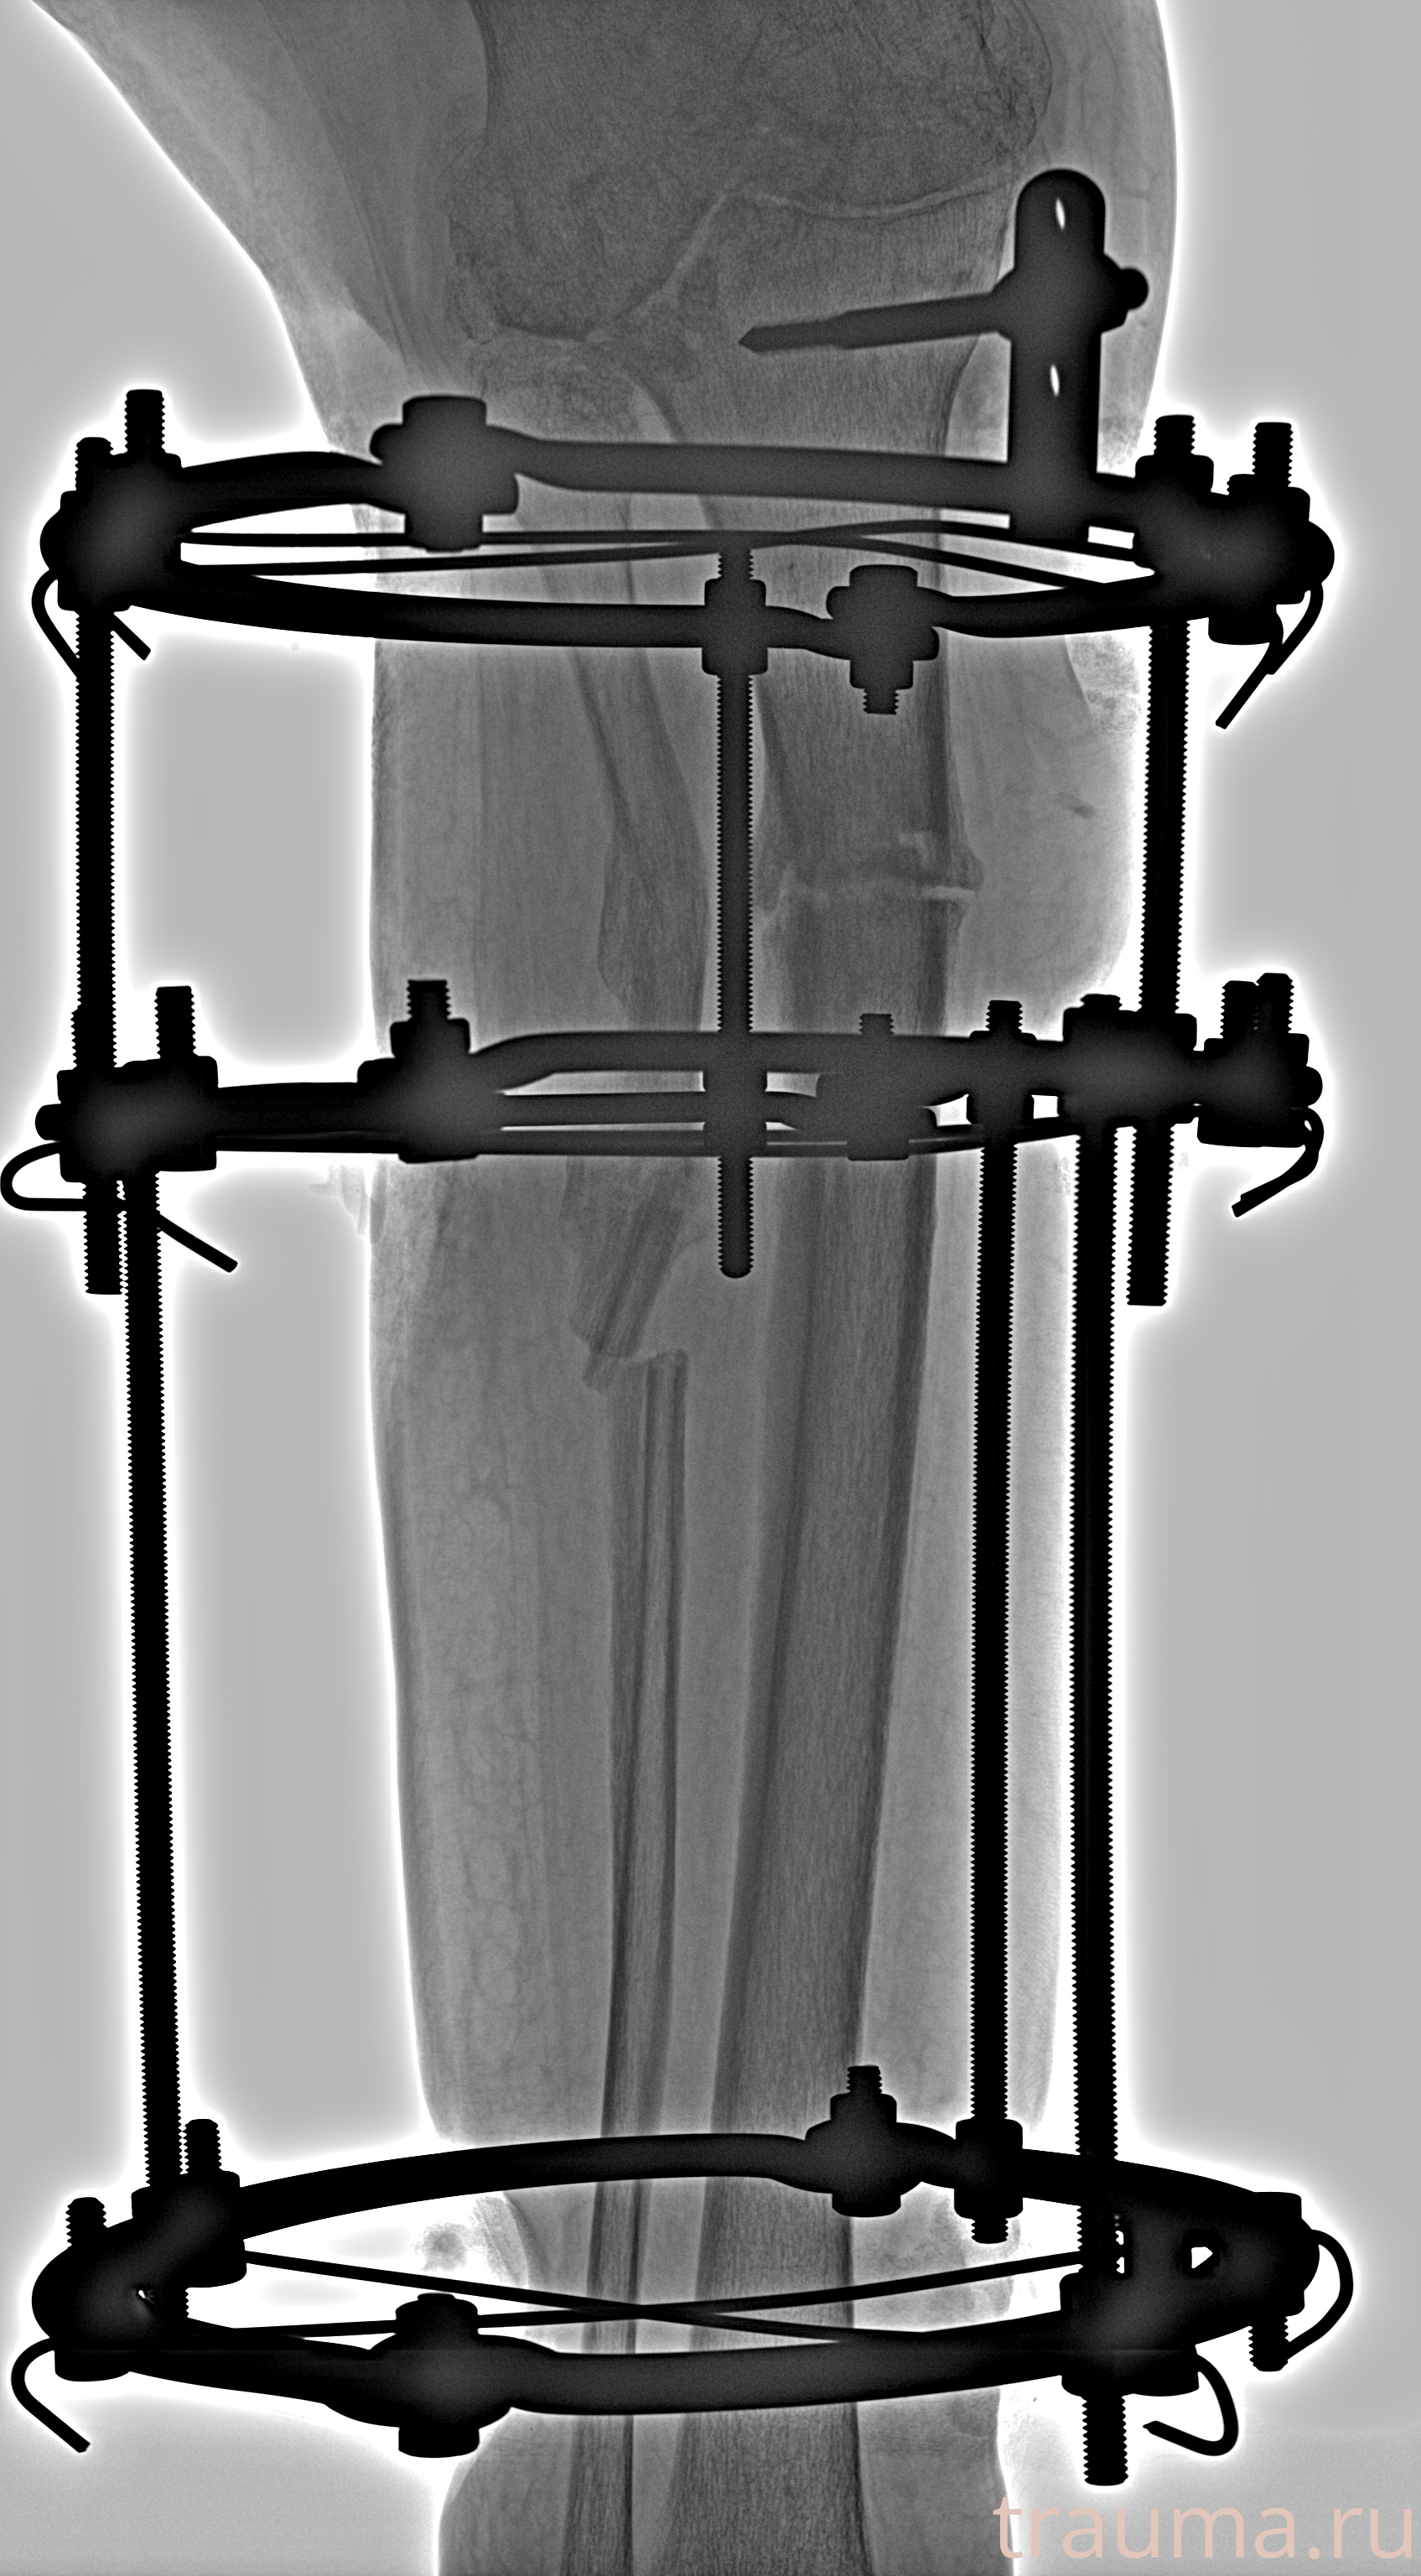

Рентгенограммы

Рентген на дому: по вашему адресу приезжает врач-рентгенолог, травматолог-ортопед с мобильным рентгеновским аппаратом, проводит диагностику травмы или заболевания, делает необходимые рентгенограммы, дает рекомендации по дальнейшему лечению. Получить качественные снимки в домашних условиях возможно благодаря уникальной методике, разработанной МосРентген Центром для института  Склифосовского